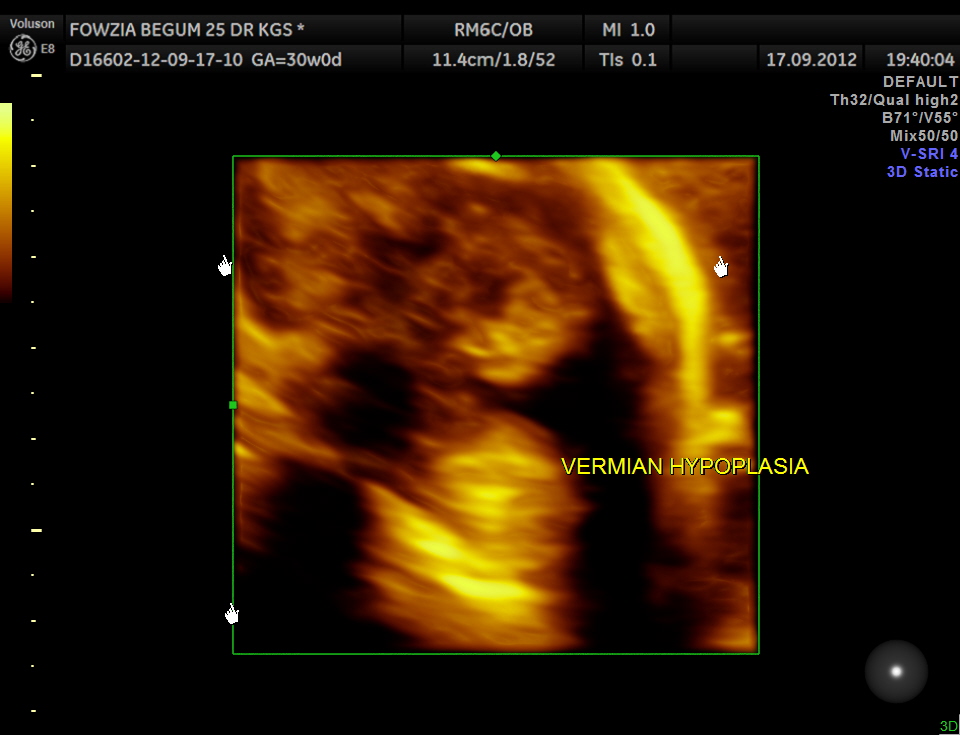

Ultrasound pictures of the fetal cranium are given below and showed cerebellar vermian dysgenesis .The buttocks sign can be appreciated.